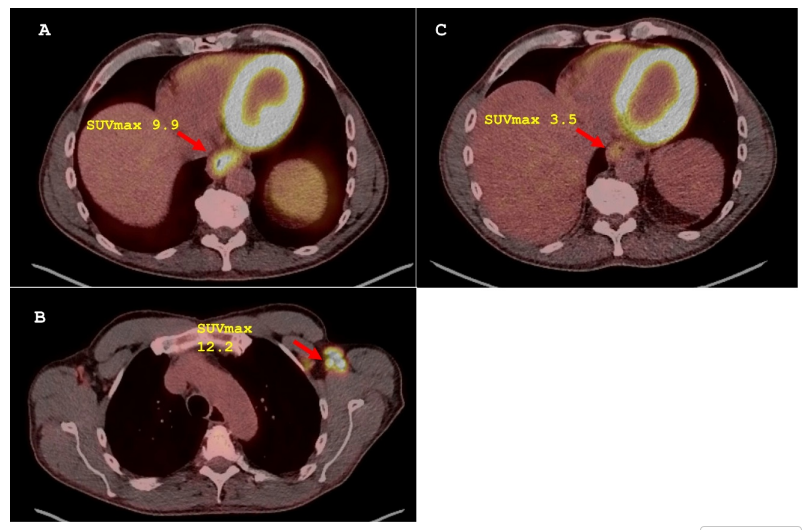

分期CT和内镜超声(EUS)及PET/CT提示GEJ及上腹部淋巴结代谢活跃,左侧腋窝淋巴结虽有代谢但在活检后证实为疫苗接种后的反应性增生(图2)。

图2. 代表性的PET图像,其SUVmax值有助于分期和评估新辅助治疗的疗效。(A) 治疗前基线PET图像显示FDG高摄取的远端食管/胃食管交界处肿块(箭头所示)。(B) 基线PET图像显示FDG高摄取的左侧腋窝淋巴结肿大(箭头所示)。(C) 诱导FOLFOX方案化疗后,同时进行FOLFOX方案化疗和放疗的PET图像显示远端食管/胃食管交界处肿块(箭头所示)代谢完全缓解。FDG表示氟代脱氧葡萄糖;FOLFOX表示氟尿嘧啶和奥沙利铂;GEJ表示胃食管交界处;PET表示正电子发射断层扫描;SUVmax表示最大标准化摄取值。